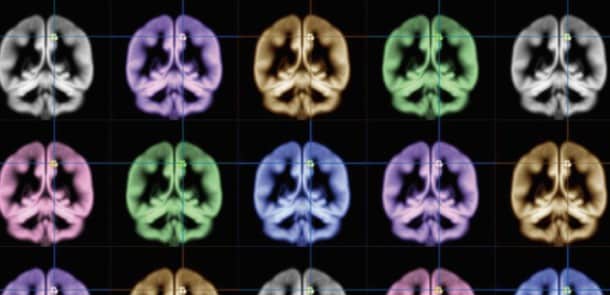

Une équipe de chercheurs de l’université de Kyoto (Japon), pilotée par Wataru Sato, s’est investie dans une enquête, associée à l’étude d’IRM, afin de prouver le lien existant entre la zone précunéus et la notion de bonheur subjectif. Rappelons que cette zone du cerveau, à laquelle il avait été attribué un rôle en termes de fonctions cognitives, se situe dans le lobule pariétal supérieur.

Afin de la mesurer, un questionnaire a été établi pour interroger les personnes sur trois critères essentiels : le ressenti des émotions, le degré de bonheur et la satisfaction de son existence. Les réponses ont ensuite été comparées avec les résultats des IRM.C’est ainsi qu’il a été remarqué que la zone précunéus des personnes jugées les plus heureuses était nettement plus développée, ladite zone contenant le plus de matière grise.